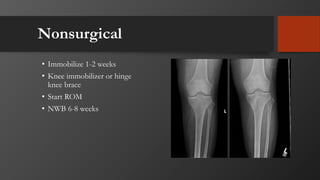

Nonsurgical

• Immobilize 1-2 weeks

• Knee immobilizer or hinge

knee brace

• Start ROM

• NWB 6-8 weeks